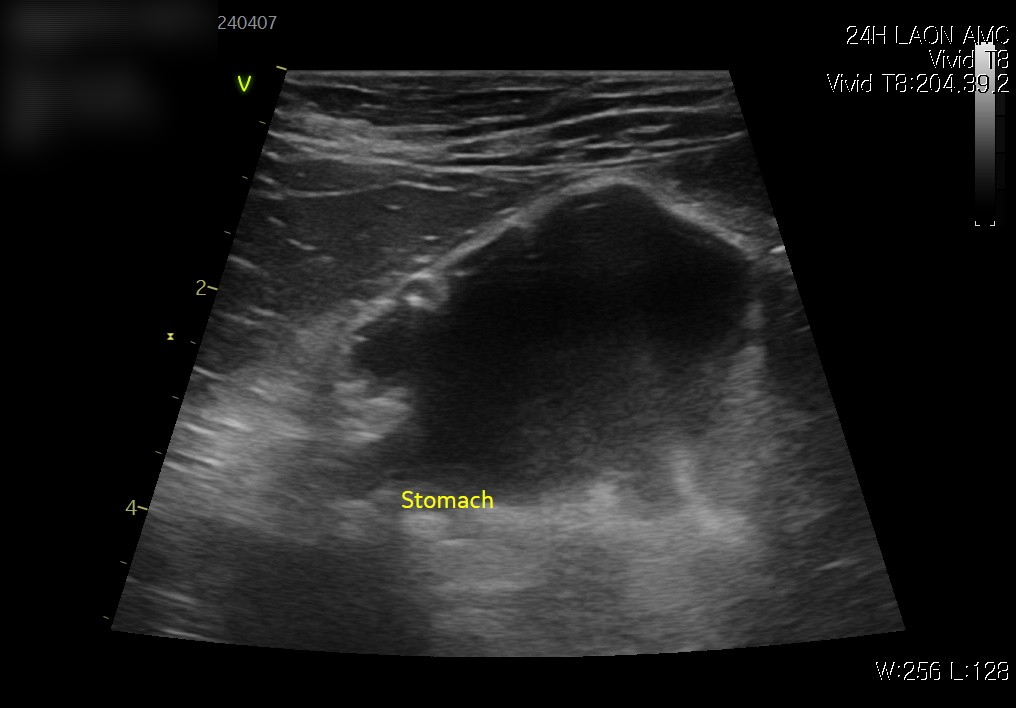

복부초음파 검사 결과

위내액체저류 확인(좌) / 이물확인(우) / 출처: 라온동물메디컬센터

초음파 검사에서 장 내에 이물 의심 소견이 확인되었고, 이물로 인해 위 내 음식물이 내려가지 못하고 저류된 상태가 관찰되었습니다.